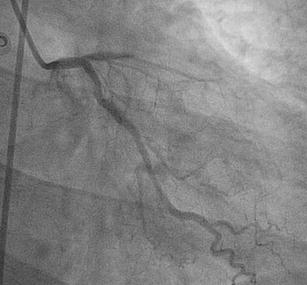

The ECG shows ST elevation in leads I, II, aVL, and V1–V6 representing acute myocardial infarction of the anterolateral wall. Coronary angiogram showed an occlusion of the mid left anterior descending artery (LAD) (Fig. 2). After reperfusion it became clear that the LAD passed over the apex, explaining the ST elevations in the inferior leads.

Fig. 2

Occlusion of the mid left anterior descending artery (LAD)